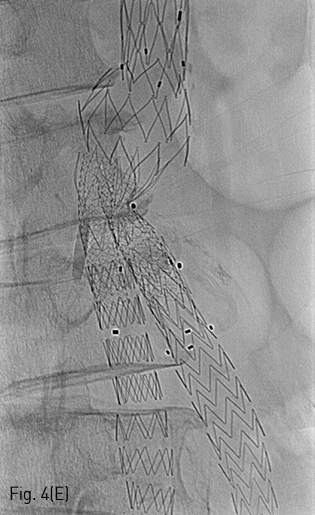

이후 우측 경로를 이용하여 AngioJet 기구를 진입시켜 2-3회에 걸쳐 혈전용해술을 시행하였고 우측 장골 분지의 내경은 회복되었다 (Fig. 4B). 이후 양측 경로에 들어있는 유도철사 (Terumo, Tokyo, Japan) 를 5Fr Berenstein catheter (Cordis, Milpitas, US) 를이용하여 Lunderquist (COOK medical, Søborg, Denmark) 유도철사로 교환한 뒤, Express LD premounted (Boston scientific, Boston, US) 스텐트를 우측은 8x37mm, 좌측은 10x37mm로 선택하여 꺽인 부위에 진입시켰다(Fig. 4C). 양측에서 조심스럽게 실시간으로 관찰하며 균형을 맞추어 스텐트를 설치하였다 (Fig. 4D). Mustang (Boston scientific, Boston, US) 9x60mm 크기의 풍선을 이용하여 설치 후 풍선확장술을 시행하여 최종적으로 스텐트의 모양을 완성하였다(Fig. 4E). 시술 직후 시행한 최종 혈관조영술 상에서 양측 분지로의 혈류가 정상적으로 회복되었으며, 혈류 속도도 양측이 균등함을 확인하였다(Fig. 5).

Fig 4E

(E) Single radiography demonstrates final result of kissing stent extension.